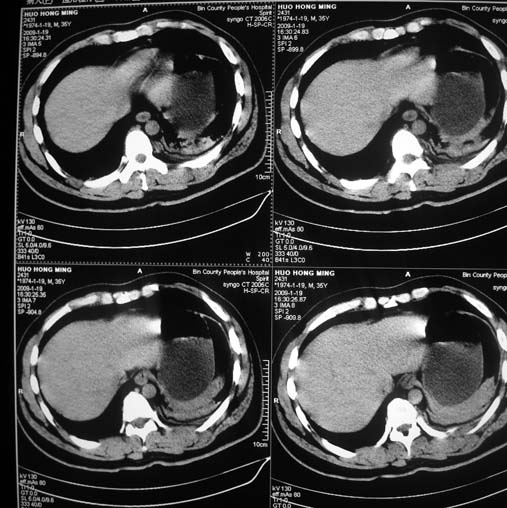

以下是引用余辉在2009-1-20 8:22:00的发言:[br]右侧肾上腺明显增大、边缘不光整,肯定有问题,结合患者病史考虑肾上腺挫伤、伴血肿形成。[br]另左肾后唇包膜下方可见局限性新月形高密度影,考虑肾包膜下出血[br]余同意楼上,建议增强排除脾破列

以下是引用随光逐影在2009-1-20 8:21:00的发言:[br]1)左侧多发肋骨及部分腰椎左侧横突骨折。2)左侧肾旁后间隙及同侧胸腔积血。3)左侧腰大肌肿胀。